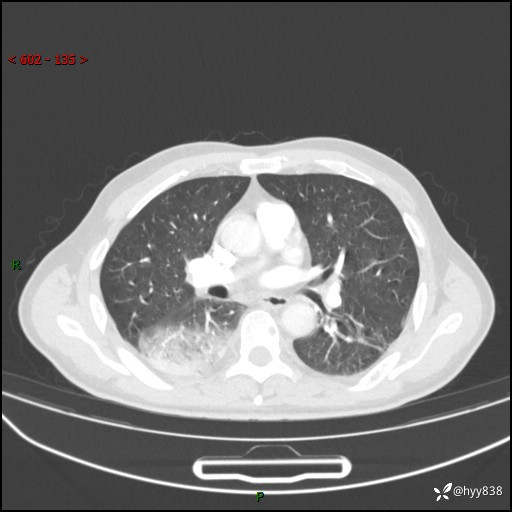

【患者信息】:63岁/男

【主诉】:发热5余天

【现病史及既往史】:患者5余天无明显诱因出现畏寒寒战发热,最高体温39.5℃,发热无明显昼夜规律,伴全身乏力、头晕,无头痛、无咳嗽咳痰、无胸痛咯血、无气短、无腹痛腹泻、无尿频尿急尿痛等不适,于当地市第五人民医院就诊,予以抗感染等治疗(具体不详)后发热无明显好转,1天前查胸部CT提示右下肺感染,为求进一步诊治,门诊以“社区获得性肺炎”收治入院; 起病以来,患者精神、食欲一般,睡眠可,大小便正常,体力体重较前无明显变化。

【检查】:胸部CT增强